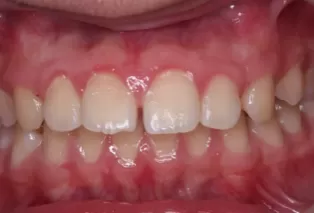

Intraoral photos after treatment